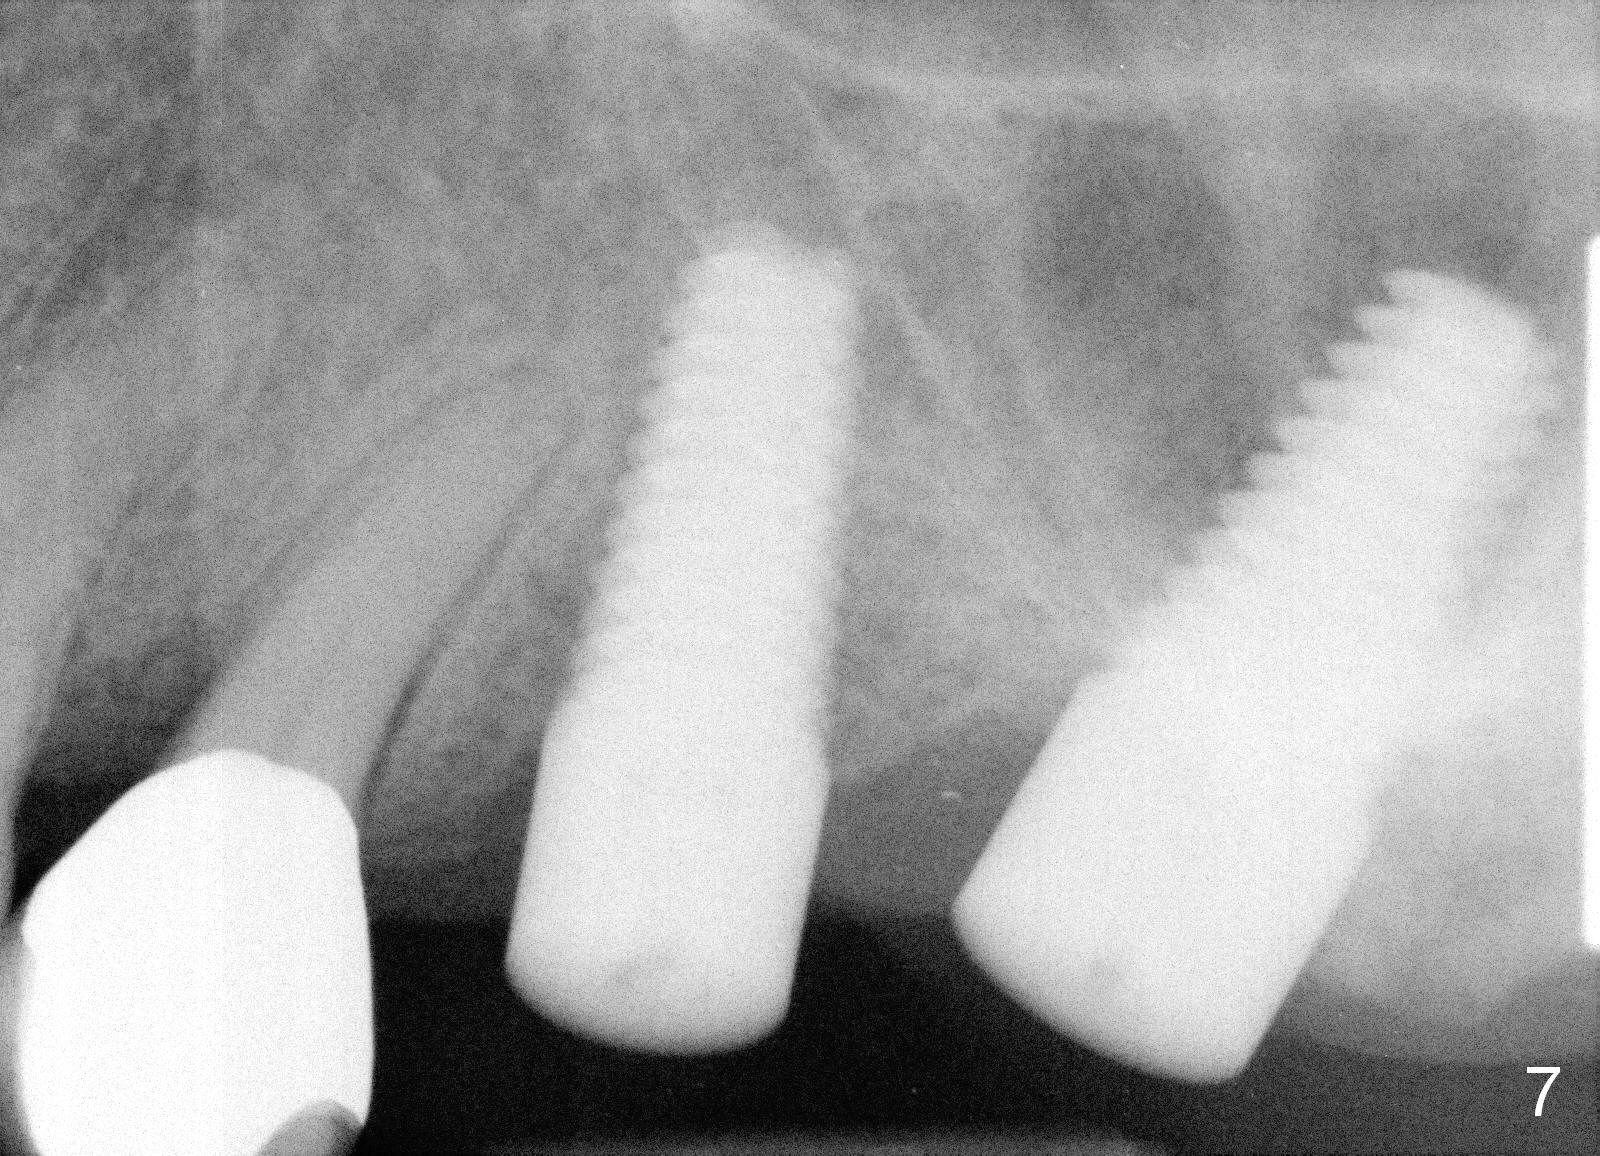

A 58-year-old man used to have a upper left 3-unit bridge. Two months after extraction and immediate implant at the site of the posterior abutment, an implant is planned to be placed at the site of the pontic, #14 (Fig.1). Osteotomy starts with a 1.6 mm pilot drill, followed by bone expanders, parallel to the crown of the tooth #13. The first intraop PA shows that 3.0 mm bone expander is close to the root of the neighboring tooth (Fig.2). No matter what is done to change the trajectory of the osteotomy using expanders according to the crown morphology of the neighboring tooth, the next 3 expander does not improve in parallelism (Fig.3). When a 6x17 mm tap is inserted (Fig.4 T), it is realized that axis of the tap is parallel to the axis of the crown of the neighboring tooth (black line), but not that of the root (red line). It is too late to change the trajectory drastically; a 6x17 mm implant is placed with insertion torque > 60 Ncm (Fig.5). It is best to change the trajectory as early as possible, e.g., after taking the first intraop PA and withdrawing the expander (Fig.6 black area) and as much as possible (red line; starting new osteotomy). It is quite similar to immediate implant. There is no bone loss 2 months postop (Fig.7), 18 months (Fig.8,9) or 34 months (Fig.10)post cementation, in spite of open contact between the crowns (Fig.10 black arrowhead). This is partially due to supragingival margin (Fig.11,12 (immediately pre-cementation)). No bone loss is noted 3 years 5 months post cementation (Fig.13).